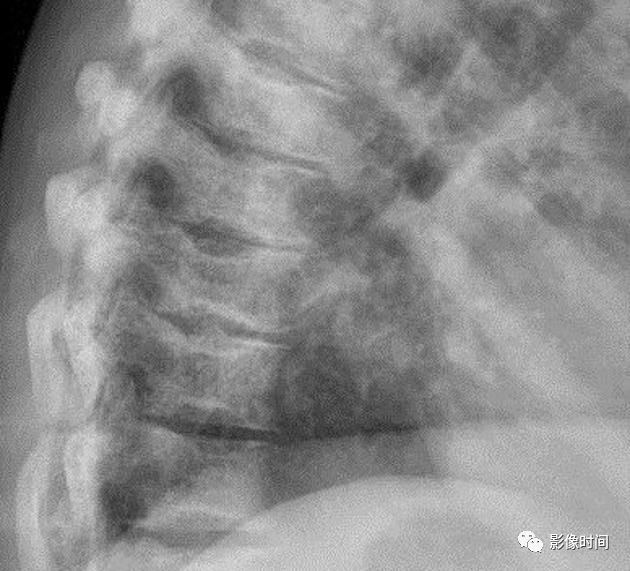

10栅栏征

栅栏征(The Palisade sign),也称灯芯绒椎体(corduroy vertebra)或灯芯绒征(corduroy sign)

脊椎椎体因病变导致骨小梁吸收、稀疏,为满足承重需要,存留的纵向骨小梁粗大;粗大骨小梁间以细条状密度减低区,形成栅栏样影像,故称栅栏征或灯芯绒椎体。

栅栏征最常见于血管瘤,以单个脊椎居多;骨质疏松如泛发性骨质增生症、老年性骨质疏松等亦可呈现此类表现,一般见于下胸椎、上部腰椎的多个椎体,只是伴有普遍的骨密度减低。有时自颈椎至腰椎全部椎体均出现栅栏征。栅栏征主要见于椎体。

典型病例

病例 1,脊柱血管瘤。胸腰椎 CT 冠状位、矢状位 MPR 重建示胸 12 椎体松质骨密度降低,其中可见粗大骨小梁呈栅栏状。

病例 2,67 岁女性,椎体血管瘤。腰椎侧位片示胸 12 及腰 3 椎体呈现栅栏征,磁共振检查证实为血管瘤。

病例 3,泛发性骨质增生症,男,47 岁。A-C.颈椎、胸椎、腰椎侧位片,显示所有椎体纵向骨小梁粗大、稀疏;粗大骨小梁间以细条状密度减低区,呈栅栏征。D-G.胸、腰椎 MR 冠状、矢状位图像,粗大、稀疏的示纵向骨小梁呈低信号,在邻近富脂肪骨髓信号衬托下呈典型的栅栏征